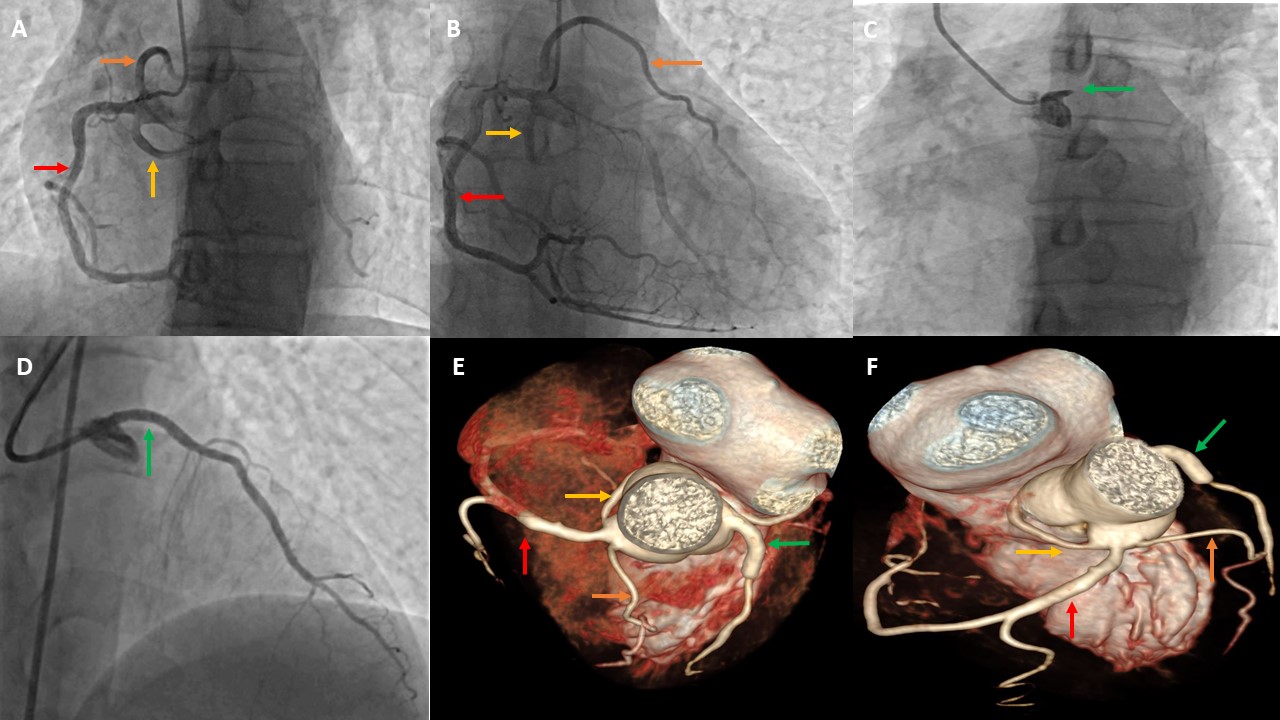

Complex Coronary Angioplasty in Jaipur – Dr. Anil Kumar Choudhary When it comes to advanced and life-saving cardiac interventions, Dr. Anil Kumar Choudhary is widely recognized as the best interventional cardiologist in Jaipur, known for his exceptional skill in performing Complex Coronary Angioplasty. Specializing in treating high-risk and difficult coronary blockages, Dr. Choudhary delivers world-class results using the latest technology and techniques. ❤️ What is Complex Coronary Angioplasty? Complex Coronary Angioplasty (also known as PCI – Percutaneous Coronary Intervention) refers to advanced angioplasty procedures used to treat challenging coronary artery blockages. These may include: Chronic Total Occlusions (CTOs) Left Main Coronary Artery Disease Severe Multivessel Coronary Artery Disease Calcified Arteries Bifurcation Lesions Restenosis (re-blockage after stenting) Unlike routine angioplasty, these cases demand high expertise, specialized tools (like rotablation, IVUS, OCT), and a deep understanding of coronary anatomy and hemodynamics. 🏥 Dr. Anil Kumar Choudhary’s Expertise in Complex PCI With a reputation for excellence in interventional cardiology, Dr. Anil Kumar Choudhary has handled some of the most complex coronary cases with successful outcomes. His approach combines: Precision and safety Use of advanced imaging (IVUS/OCT) for lesion assessment Rotablation & atherectomy for hard, calcified plaques Bifurcation and multivessel stenting techniques Experience in left main coronary angioplasty 🚨 When is Complex Angioplasty Recommended? Dr. Choudhary may suggest complex angioplasty in cases such as: Patient is not suitable for bypass surgery (CABG) High-risk or elderly patients with multiple blockages Blockages in critical arteries like the left main artery Patients with diabetes or weak heart function (low ejection fraction) Previously failed angioplasty or re-narrowing of stents 🔬 Advanced Tools & Techniques Used by Dr. Choudhary IVUS (Intravascular Ultrasound) – for accurate visualization inside arteries OCT (Optical Coherence Tomography) – to guide precise stent placement Rotablation – for drilling hard, calcified plaques Dual-stenting techniques – for complex bifurcation lesions Drug-eluting stents (DES) – to reduce re-blockage risk ✅ Why Choose Dr. Anil Kumar Choudhary for Complex Coronary Angioplasty in Jaipur? 🩺 Over a decade of experience in complex and high-risk PCI 🏥 Advanced Cath Lab with cutting-edge imaging tools 💯 High success rate in critical cases 👨‍⚕️ Personalized treatment planning and post-procedure care 💬 Transparent patient communication and ethical practice Recognized as the best cardiologist in Jaipur for complex interventions ❤️ Conditions Treated with Complex Angioplasty Chronic Total Occlusion (CTO) Triple Vessel Disease Left Main Coronary Artery Blockage Coronary Artery Calcification Bifurcation and Trifurcation Lesions Stent Restenosis Low LVEF with CAD Unstable Angina or Heart Attack 📍 Visit the Best Heart Specialist in Jaipur for Complex Coronary Care If you've been advised bypass surgery or have been diagnosed with multiple or complex blockages, consult Dr. Anil Kumar Choudhary for a second opinion. Many patients have avoided open-heart surgery through his expert complex angioplasty.

Complex Coronary Angiography in Jaipur – Dr. Anil Kumar Choudhary If you're suffering from chest pain, breathlessness, or have been diagnosed with multiple or difficult heart blockages, Complex Coronary Angiography is the first and most crucial step in your treatment journey. Dr. Anil Kumar Choudhary, the best interventional cardiologist in Jaipur, offers expert-level precision in performing this life-saving diagnostic procedure. With vast experience in advanced cardiac imaging and diagnosis, Dr. Choudhary provides highly accurate and detailed coronary assessments, especially in patients with multiple blockages, previous bypass surgeries, diabetes, or high-risk profiles. 🩺 What is Complex Coronary Angiography? Coronary Angiography is a diagnostic procedure that uses a special contrast dye and X-ray imaging to visualize the arteries supplying blood to your heart. In complex cases, this procedure is performed with advanced imaging techniques and requires high-level expertise to interpret intricate blockages or anomalies. Complex Coronary Angiography is typically needed when: There is suspected multi-vessel disease The patient has chronic total occlusions (CTOs) There’s history of previous stents or bypass surgery (CABG) The patient has diabetes, kidney disease, or low ejection fraction (LVEF) Symptoms are unusual, prolonged, or high risk 🔬 Dr. Anil Kumar Choudhary’s Expertise in Complex Angiography Dr. Choudhary is known for his high diagnostic accuracy and sharp interpretation of even the most challenging coronary cases. His use of intravascular imaging tools such as: IVUS (Intravascular Ultrasound) OCT (Optical Coherence Tomography) FFR (Fractional Flow Reserve) ensures detailed visualization and functional analysis of blockages. This level of precision helps in planning the most appropriate and safe intervention, whether it be angioplasty, stenting, or surgery. 💡 Benefits of Choosing Dr. Anil Kumar Choudhary for Complex Coronary Angiography 🏥 Advanced Cath Lab with high-resolution imaging systems 🎓 Expert in diagnosing complex coronary artery disease (CAD) 🧠 Deep understanding of hemodynamics and coronary physiology 💯 Helps avoid unnecessary stenting through accurate lesion assessment 🩺 Specialist in post-bypass and restenosis case evaluation ✅ When is Complex Coronary Angiography Recommended? Recurrent chest pain or angina despite medication Suspicion of triple vessel disease or left main artery blockage Previous CABG (bypass surgery) or angioplasty patients Cases with diabetes, chronic kidney disease, or heart failure Prior equivocal stress test or CT angiography results Evaluation of in-stent restenosis or stent failure ❤️ Why Dr. Anil Kumar Choudhary is the Best Cardiologist for Complex Angiography in Jaipur 👨‍⚕️ Over a decade of interventional cardiology experience 💻 Use of cutting-edge technology and imaging tools 🧪 Expertise in high-risk and redo cases 🤝 Patient-centric care with ethical and transparent consultation 📈 High diagnostic precision ensuring targeted treatment planning 📍 Visit Jaipur’s Best Coronary Angiography Specialist Today Don't leave your heart health to chance. If you or your loved one has symptoms of serious heart disease or complex cardiac history, trust Dr. Anil Kumar Choudhary, the most reliable name for complex coronary angiography in Jaipur.